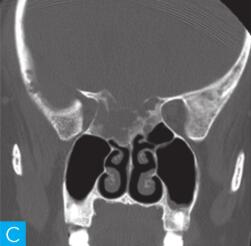

CT检查:检查设备为16层CT,病人采取仰卧位,扫描范围包括双侧鼻窦。扫描参数:层厚2.5mm,120kV,150mA,矩阵512×512。观察图像:软组织窗窗宽300HU,窗位60HU;骨窗窗宽2000HU,窗位400HU,见图1。

图1 鼻窦CT:A. CT横断面(骨窗);B. CT横断面(软组织窗);C. CT冠状面(骨窗);D. CT冠状面(软组织窗)

答案A 解析:结合CT横轴位及冠状位图像,该病变位于后组筛窦,不难判断。

答案D 解析:该病例病变周围骨质在原有后组筛窦结构基础上出现轻度的骨质膨胀性改变,周围骨质可见明显硬化,故D为最佳答案。

CT平扫示后组筛窦区见轻度膨胀性骨质破坏,内部密度混杂,可见斑片状、分隔状骨质密度影,部分呈磨玻璃改变,病变边缘清晰,可见薄层骨壳及硬化边。

(2)定位诊断:

对于本病例来说,病变定位不困难,病变主体位于后组筛窦区。

本病例CT上特点为轻度膨胀性压迫性骨质吸收,边缘骨质见硬化边,呈薄层骨壳表现,提示肿瘤良性可能;病变内部密度不均匀,可见骨性间隔及斑片状磨玻璃骨性密度影,提示病变可能为骨纤维源性肿瘤或肿瘤样病变。

本病例的临床表现无特异性。影像学表现具有一定特征性,具有诊断价值。病变主体位于后组筛窦,精准的病变定位是该病例的诊断前提。病变区骨质呈轻度膨胀性骨质破坏,边缘可见明显硬化边,提示病变进展缓慢,是良性病变的特征。另外,CT显示病变内部有大量磨玻璃样高密度影,提示病变区存在纤维化骨的成分,是骨纤维源性肿瘤或肿瘤样病变的重要影像学征象。结合病变发生的部位,好发于颅面骨的骨纤维源性良性肿瘤常见有骨化性纤维瘤、骨纤维异常增殖症。本例不支持骨纤维异常增殖症的地方在于,后者发生在颅面骨时一般呈多骨受累改变,同时病变本身骨质膨胀变形更明显。